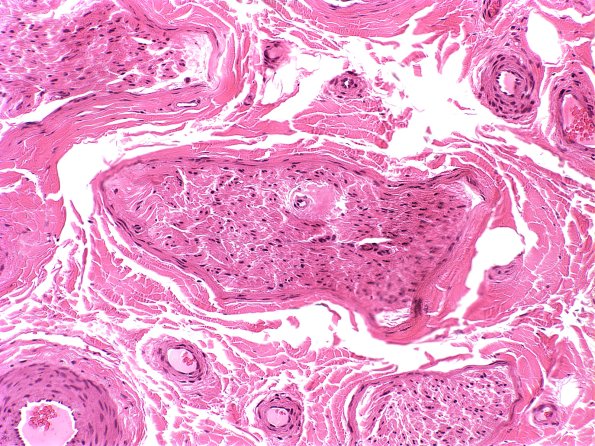

21A1 Amyloid neuropathy (Case 21) H&E 1